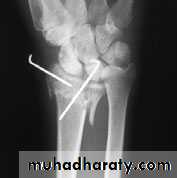

3-IMPACTED OR COMMINUTED COLLES’ FRACTURESWith substantial impaction or comminution in osteoporotic bone, manipulation and plaster immobilization alone may be insufficient. The fracture can sometimes be reduced and held with percutaneous wires, but if impaction is severe even this may not be enough to maintain length; in that case, an external fixator is used to neutralize the compressive force of the 25 tendons crossing the wrist, and bone graft or bone substitute is placed into the gap. The fixator is attached to the distal radius and the second metacarpal shaft.

IMPACTED OR COMMINUTED COLLES’ FRACTURES